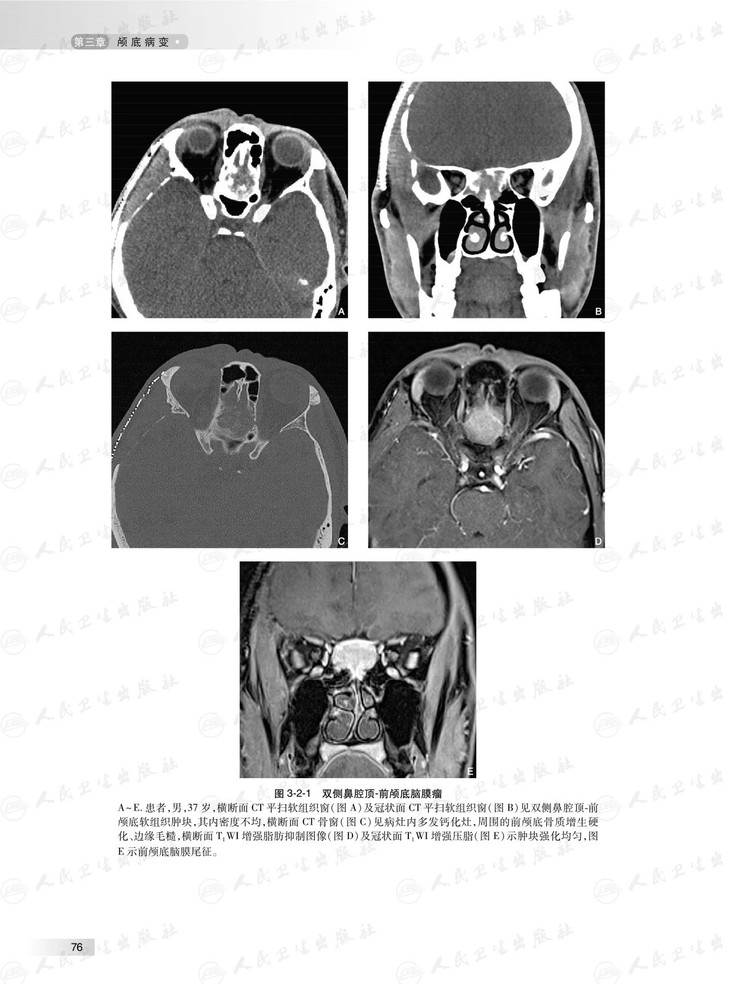

本书根据头颈部影像临床工作场景,对头颈部影像学征象或表现进行系统讲解和分析,头颈部包括的部位多,结构复杂细微,病变种类繁杂,每个部位的影像学征象和表现各有特点,据此,本书按照颅底、耳部、鼻腔与鼻窦、眼球与眼眶、咽喉部、口腔、颌面部、舌骨上颈部间隙和舌骨下颈部间隙等部位各成一章。头颈部外伤性病变有其自身特点,故独立成章。本书图文并茂,具有全面、系统、简洁和清楚的特点。